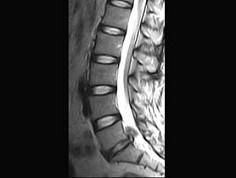

问题 男,50岁,有腰腿疼痛2个月,疼痛可向左下肢放射,请结合所提供图像,选出最佳选项 ( )

选项 A、L/S椎间盘膨出 B、L/L椎间盘膨出 C、L/L椎间盘突出 D、椎间盘变性 E、L/S椎间盘突出

答案 E